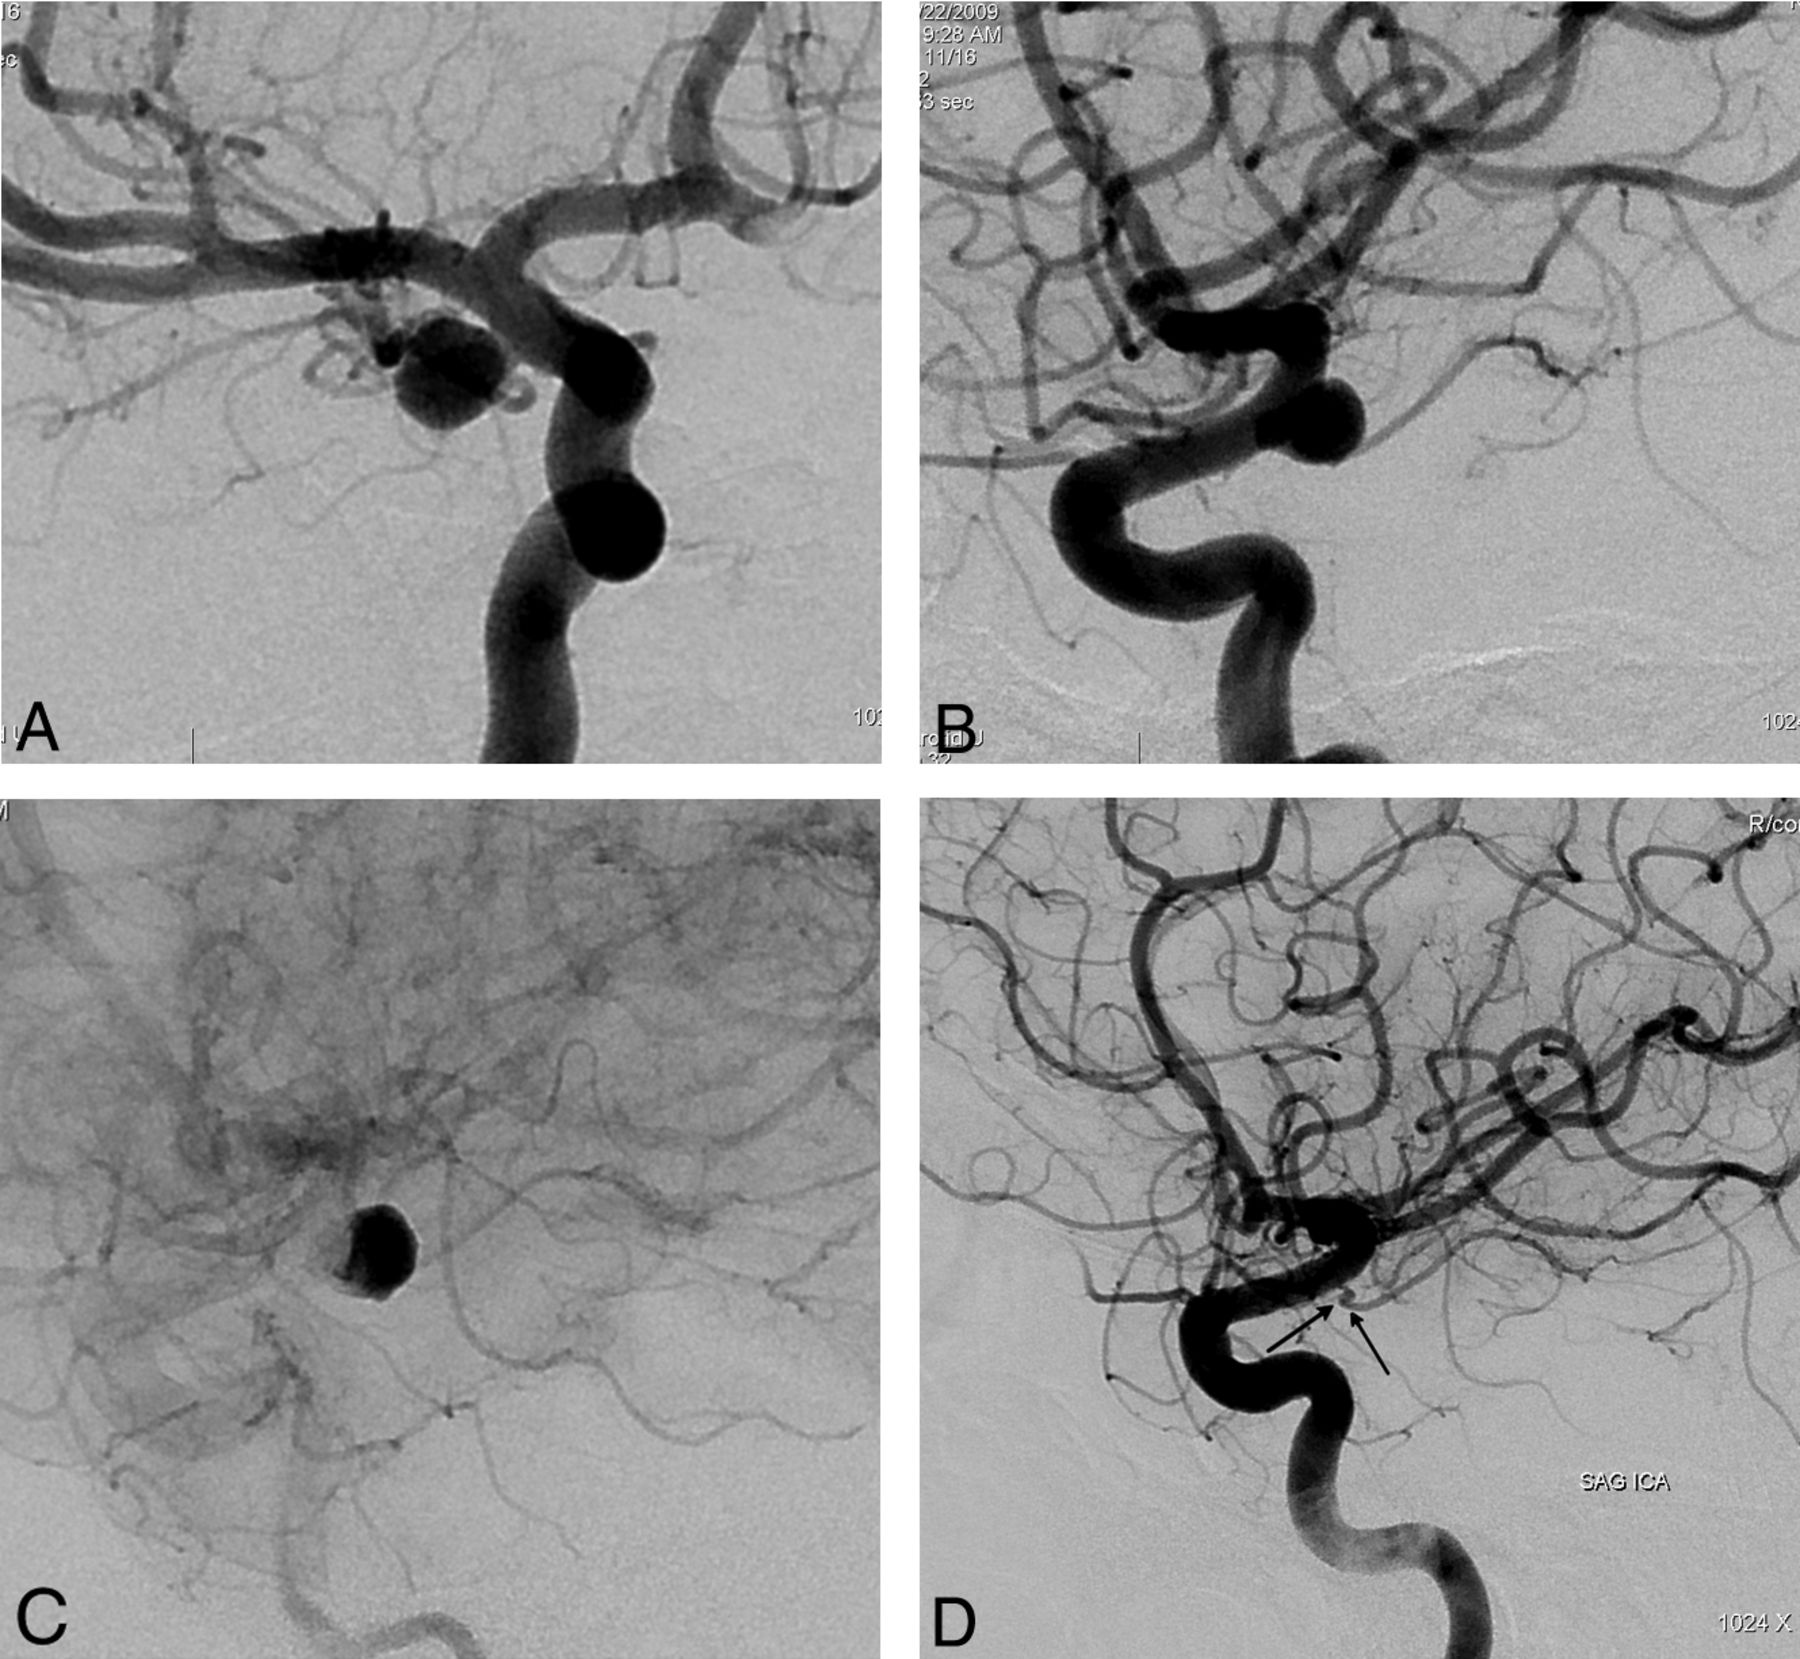

This retrospective study included 251 aneurysms treated with PEDs in 191 consecutive patients (mean age, 49.2 years; age range, 26–71 years; except for 1 pediatric patient who was 13 years of age) between November 2008 and September 2011. One hundred twenty-nine patients were female and 62 were male. Following ethics committee approval, 17 of the patients were included in the Pipeline for Uncoilable or Failed Aneurysms Study. Written informed consent was obtained from each patient. Sidewall aneurysms with wide necks (≥4 mm) or unfavorable dome-neck ratios (≤1.5) (Fig 1), large or giant aneurysms that might have or already had mass effect (Fig 2), fusiform aneurysms (Fig 3), blisterlike aneurysms (Fig 4), recurrent sidewall aneurysms, dissecting aneurysms (Fig 2), aneurysms at difficult angles to the parent artery (so that catheterization of the aneurysm and coiling may have increased risk) (Fig 5), and aneurysms in which a branch was originating directly from the sac (therefore endosaccular obliteration or clipping was likely to compromise the branch or result in a neck remnant) were treated with the PED (Figs 6 and 7). We intended to treat 1 patient with a giant, very wide-neck, cavernous ICA aneurysm presenting with mass effect symptoms by using a PED; however, we failed to bypass the neck of the aneurysm, resulting in treatment of the aneurysm with parent artery occlusion following a balloon occlusion test, without complications. This patient was not included in the study because a PED was not used. This was the only technical failure during the course of the series.

Preoperative 2D (A and B) angiograms show the ICA aneurysm in which the anterior choroidal artery is originating from the aneurysm at the neck. A single PED is placed covering the neck, causing stagnation of the contrast within the sac (C). Six-month control angiography (D) demonstrates total occlusion of the aneurysm with the anterior choroidal artery preserved (arrow).

Two patients developed ipsilateral remote intraparenchymal hematomas. The first patient's hematoma developed within the first 8 hours after treatment (Fig 1). This hematoma was attributed to overmedication. The patient was placed on subcutaneous low-molecular-weight heparin despite her very high response to clopidogrel (the VerifyNow level was 97%) because the artery was reconstructed by using 16 devices overlapping in a telescopic fashion and we were worried about thromboembolic complications due to metal overload. The patient did not have any permanent neurologic sequelae from this event and was discharged home after 1 week. Control angiography showed total obliteration of the aneurysm with the parent artery reconstruction.